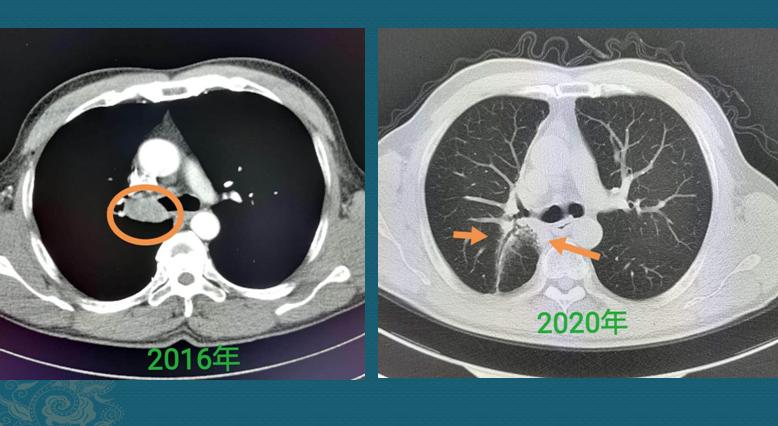

就像上面这位病人,CT发现左下肺分叶状实性肺结节,不能排除肺癌,尤其是鳞癌和小细胞,当然也可能是良性肿瘤(比如错构瘤),可以考虑进一步增强CT或者穿刺确诊。

他没有做进一步检查,选择听天由命,结果10年后因为其它原因复查CT,结节没有明显变化,符合良性肿瘤的特点。

这种情况只能说当年没有确诊,不能说是误诊。